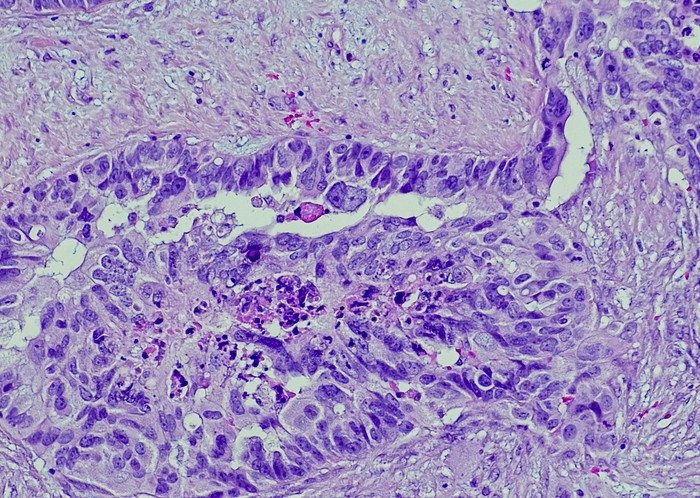

Featured photo at top of ovarian cancer cells. Photo/OGPhoto/iStock.